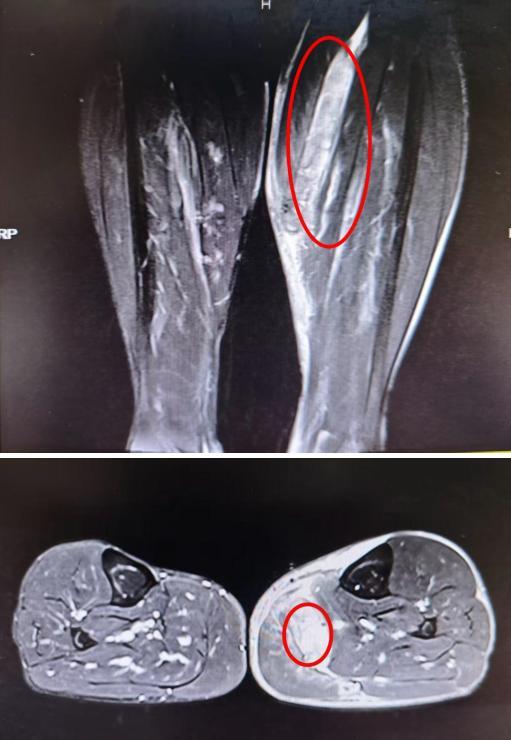

着急的李先生来到湖南旺旺医院骨一科就诊,经关节镜与运动损伤专科主任肖勇检查后确诊为:腓肠肌内侧头撕裂合并血肿形成。

(▲核磁共振显示:腓肠肌内侧头撕裂,血肿形成。)

因血肿体积较大,患者最终接受了血肿清除手术。术后经过规范的康复训练,李先生的小腿肿痛终于消退,重新找回了跑步的快乐。